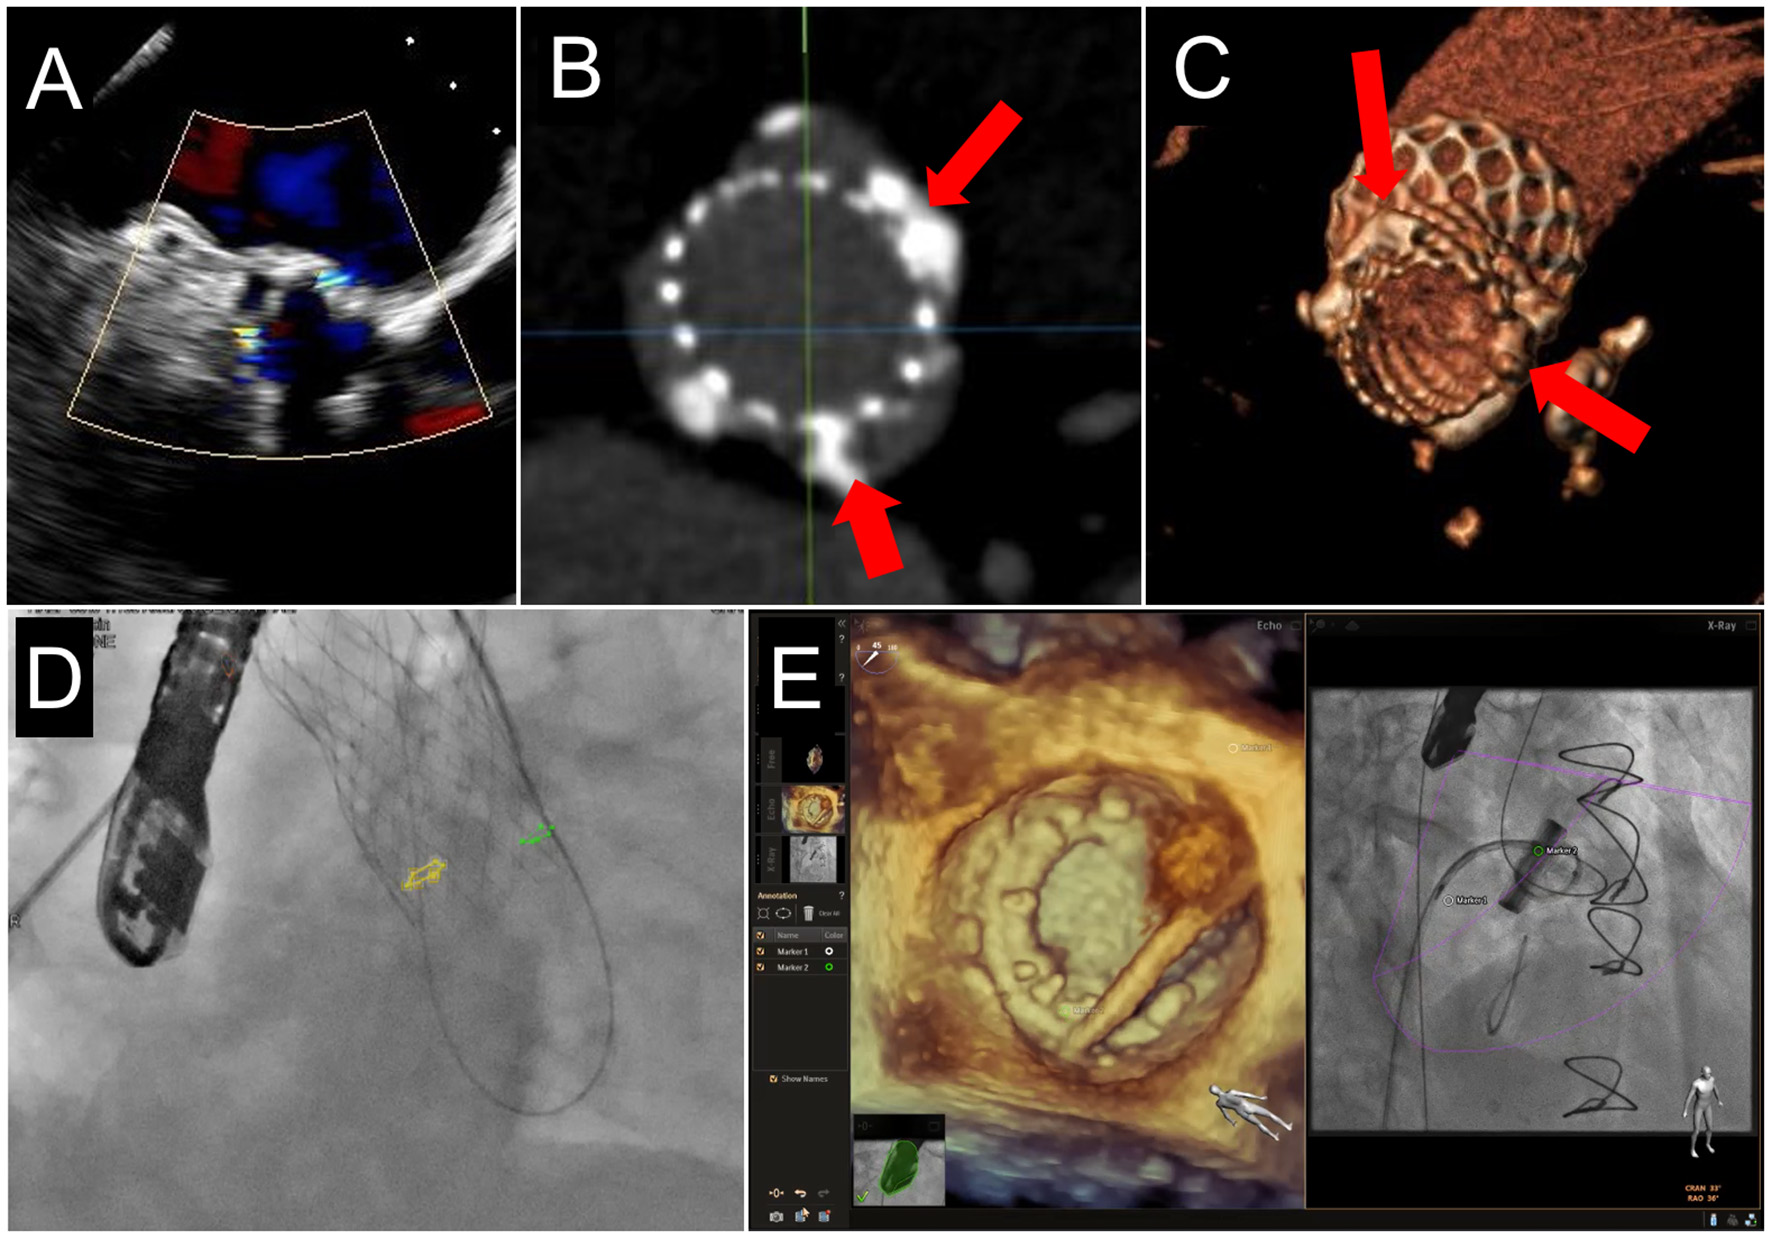

Position is key in device stability and reducing the risk of LVOTo. Positioning the THV too apically can compromise LVOT flow, whereas deploying too atrially can compromise device stability and risk embolization. For ViR or ViMAC utilizing a balloon-expandable Sapien 3 THV, it is generally desirable to have ~80% of the valve stent in the LV and 20% in the LA. During deployment, the balloon-expandable THV shortens almost exclusively from the inflow (atrial) side; therefore, the landing zone is assessed based on the ventricular edge of the stent. For ViV TMVR, it is generally recommended to align the ventricular edge of the THV frame with the ventricular edge of the existing bioprosthesis, which can be assessed by fluoroscopic markers and TEE, but this positioning can be altered based on the risks of LVOTo vs. atrial embolization, as well as the intended degree of valve expansion (37, 45, 47). In mitral bioprostheses and rings with few fluoroscopic markers, TEE fusion can help optimize the depth of TMVR implantation (Figures 7D,E). Positioning of the investigational valves for TMVR in a native mitral annulus will depend on the specific device design and morphology. Anchoring mechanisms for existing devices include ventricular tabs, radial force, atrial and ventricular disks, annular or subvalvular docks, among others. The full discussion of investigational devices for TMVR in native mitral annulus is beyond the scope of this review. To optimize visualization of the device trajectory and coaxiality, simultaneous biplane imaging is performed from the mid-esophageal commissural view (40–70°) to assess the medial-lateral position and the mid-esophageal long-axis view (120–150°) to assess the anterior-posterior position. Live 3D multiplanar reconstruction (MPR) allows for more accurate alignment of the echocardiographic planes with the device and delivery system during device positioning and deployment. However, 3D TEE reduces frame rate, which may be overcome by decreasing the sector size, adjusting the spatial resolution, and utilizing multi-beat acquisition.

Figure 7

Fusion Imaging. 2 PVL jets are seen on TEE color Doppler imaging in a patient who had previously undergoing TAVR (A). These were anatomically located on subsequent CCTA (B,C, red arrows) and co-registered onto fluoroscopic procedural imaging (D, yellow and green circles). (E) A mitral PVL closure using live TEE fusion imaging for co-localization.

The first consideration for intraprocedural guidance is the location of the transseptal puncture. Lateral and anterior jets are the most accessible from multiple puncture sites. Posterior and medial jets are more challenging and require careful consideration of transseptal puncture location on a case-by-case basis (Figures 11A–D). While the general location of the jet may be accessible in a posterior or medial defect, the direction through which to cross the defect will be more complex. A steerable sheath allows significant flexibility; however, for entry into the defect, a catheter with a greater bend may be required to approach the defect with a favorable trajectory. For defects that are difficult to cross via a transseptal route, retrograde access may provide an easier option (Figures 11E–G). Transapical access may also be considered for greater support, with the tradeoff of a more invasive approach. Correlative or fusion imaging with CCTA may help better understand the relationship of the PVL with fluoroscopic views and reduce the procedural time (Figures 7A–D) (54). Care should be taken to avoid transseptal puncture near the interatrial or atrial-caval grooves, to avoid atrial perforation and potential cardiac tamponade.